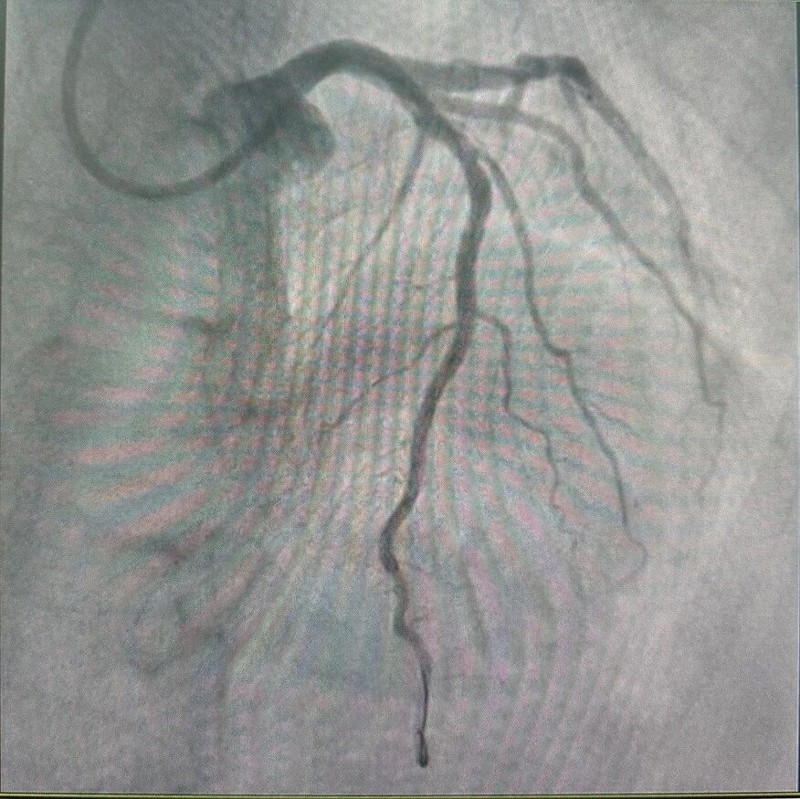

“双梗并发,嗜酸为祸”——特发性嗜酸粒细胞增多症并发心肌梗死与脑梗死一例